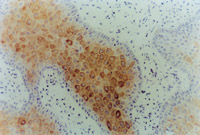

MEBT/MEBO治療30天后,再生修復(fù)的上皮組織進(jìn)行細(xì)胞角質(zhì)素AE3檢查為陽性,表皮顆粒層細(xì)胞質(zhì)呈棕色染色,細(xì)胞核呈藍(lán)色(圖5-3-9~5-3-6),證實(shí)為自身再生的復(fù)層鱗狀上皮。

5-3-9 MEBT/MEBO治療30天,細(xì)胞角質(zhì)素AE3呈陽性。(說明患者燒傷創(chuàng)面是自我再生修復(fù)) HE×20

5-3-10 同上  HE×40